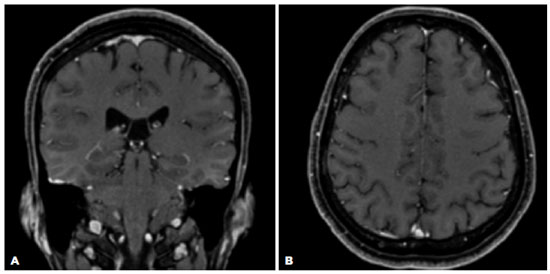

Admission for intravenous administration of aqueous crystalline penicillin G for 14 days followed, with gradual improvement of signs and symptoms throughout hospitalization (Figure 3A and B). Two months after the treatment, the patient’s VA was 20/20 in OU, resolution of the RPE nodularities was observed on OCT (Figure 3C and D), and complete resolution of the dural enhancement and skull lesion were visualized on MRI (Figure 4). Follow-up in the ophthalmology and infectology departments were maintained.